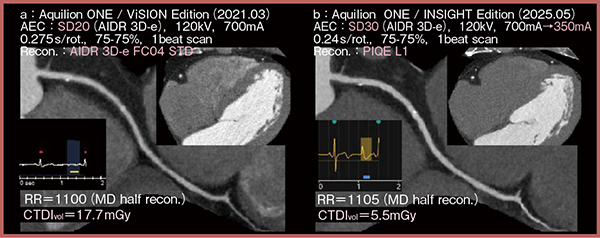

症例2は56歳,男性,狭心症疑いの症例で,BMI:25.6とやや肥満傾向である。新基準条件における算出線量が700mAであったため,Aquilion ONE / INSIGHT Edition(図3 b)ではその半分の350mA(旧基準条件の1/4線量)で撮影したところ,旧基準条件の画像(a)と比べて被ばく線量がCTDIvol:17.7mGyから5.5mGyへと大幅に低減し,かつノイズは良好に抑制され,血管辺縁も明瞭であった。

図3 症例2:狭心症疑い